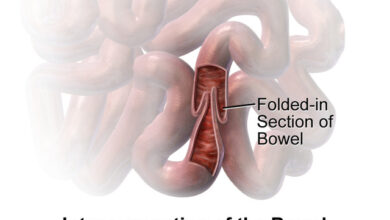

Management Of Intussusception In Children

Intussusception (in-tuh-suh-SEP-shun) is a serious condition in which part of the intestine slides into an adjacent part of the intestine.…